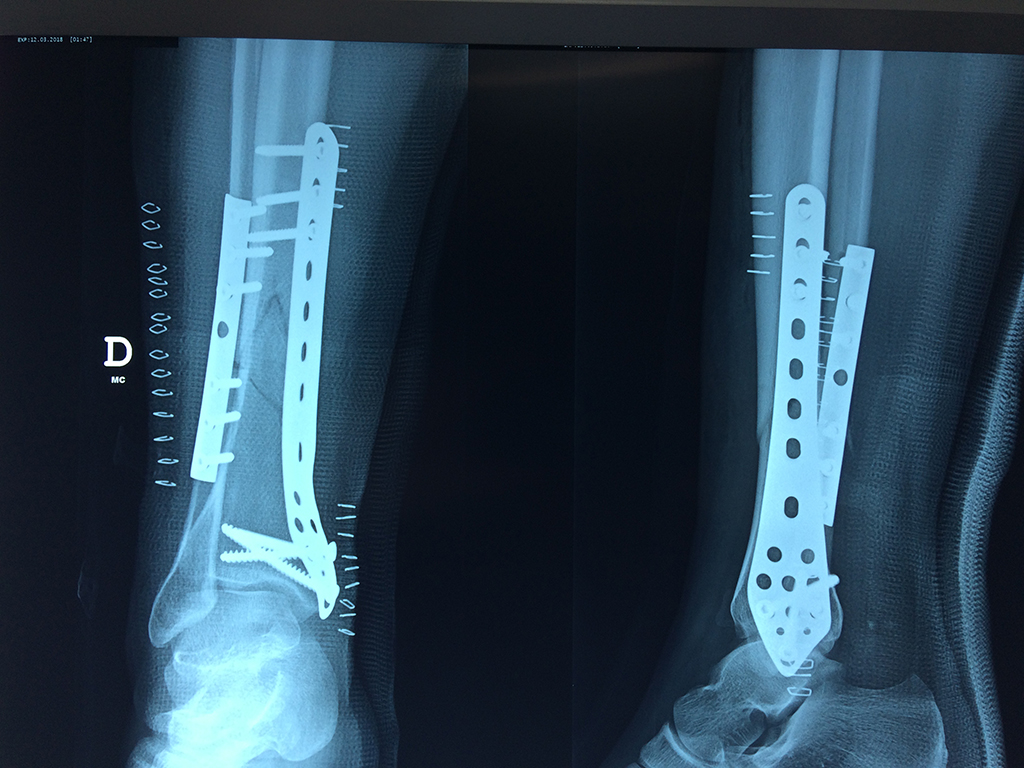

Cirugías de Peroné y Tibia

Aunque cada uno de estos huesos puede fracturarse por separado, normalmente la rotura es una lesión que se produce de forma conjunta

La mayor parte de las roturas implican a la parte proximal del hueso (parte del hueso próximo a la rodilla) o a la parte distal (parte del hueso cerca del tobillo).

Debido a la fina cobertura de piel que recubre la tibia y el peroné, las fracturas generalmente son abiertas, es decir, el hueso roto rasga la piel, atravesándola. Las fracturas de tibia y peroné generalmente se producen por un fuerte impacto o torsión.